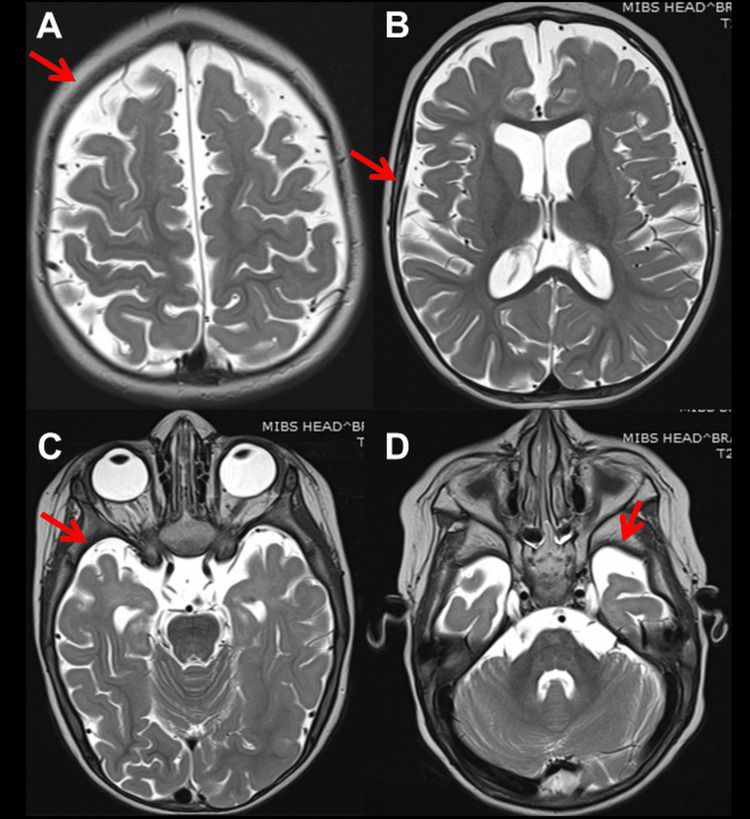

At 12 months of age, she experienced a second SE, again terminated by DP, hydroxy-butyrate, and TP. VPA was switched to phenobarbital (PB). EEG at 15 months showed general slowing, delta activity across the occipital projections, and regional spikes along with delta bursts over O2-T6. At 16 months of age, she suffered a third SE, so PB was switched to oxcarbazepine (OXC), which was discontinued after seven days for ineffectiveness and replaced with perampanel (PER) in monotherapy (Table 3). EEG showed general slowing and focal seizure activity across F3-C3 associated with the eye version to the right. Post-ictal lethargy and decreased motivation occurred. Neurological evaluation after recovery revealed generalized hypotonia, discoordination, unstable eye contact, drooling, open mouth, and ankle contractions. She liked watching cartoons and playing with water. At 27 months of age, clonazepam (CZP) was added to PER with no beneficial effect (Table 3). Subsequently, ethosuximide (ESM) was added to PER but discontinued after 14 days due to ineffectiveness (Table 3). Cerebral magnetic resonance imaging (MRI) at 27 months of age showed bilateral diffuse cortical and subcortical atrophy (Figure 1) and incomplete myelination (Figure 2). At 33 months of age, levetiracetam (LEV) was tried but discontinued after four weeks because of ineffectiveness (Table 3). At 34 months of age, clobazam (CLB) was added to PER but stopped because daily seizures recurred. At 36 months of age, there was still no head control, but she had periodic torticollis to the left, tetraspasticity, increased tendon reflexes, positive pyramidal signs, and widespread hyperkinesia most pronounced in the left shoulder and unrelated to EEG activity. Topiramate (TPM) and hydrocortisone were started and PER was discontinued, stopping seizures for the next 40 months (Table 3). At the age of 40 months, she was switched to therapy with PER and TPM (Table 3).

The index patient also presented with intractable epilepsy, myocloni, psychomotor regression, tetraspasticity, and torticollis. Epilepsy presented with generalized tonic-clonic seizures and focal seizures. Myocloni were not associated with epileptiform discharges. Various seizure types have been reported in NARS2-related disorders. These include focal, generalized, epileptic spasms, infantile spams, myoclonic seizures, absences, and SE [ref. 1]. EEG findings can range from background rhythm slowdown, focal or multifocal spikes/multiple spikes, and hypsarrhythmia [ref. 1]. Cerebral imaging may show hydrocephalus, cortical and subcortical atrophy, white matter lesions, basal ganglia lesions, or subdural hematoma [ref. 1]. The index patient benefited most from VPA, steroids, and PER. All other AEDs were ineffective or only temporarily effective.